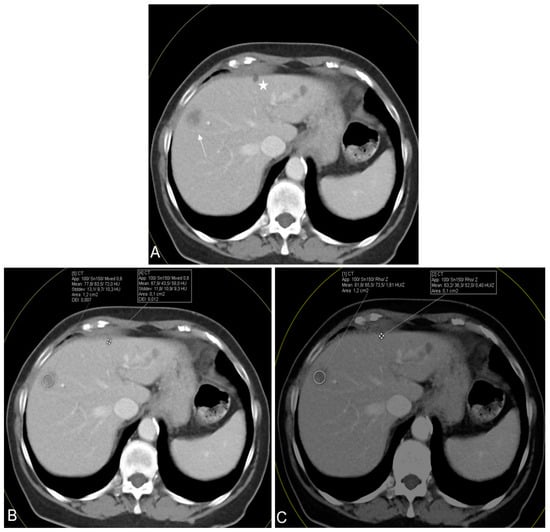

In Figure 5, an exemplary CT scan of a patient reveals multiple hypodense liver lesions in the context of malignant melanoma. Despite the acquisition of HU measurements, distinguishing between these lesions proved challenging. Nevertheless, a clear diagnosis remained challenging, which is why Rho/Z maps were derived.

Figure 5. Axial contrast-enhanced CT scan in a 54-year-old female suffering from malignant melanoma. The scan showed multiple hypodense liver lesions in different segments, including a biopsy-confirmed liver metastasis in segment 8 (arrow) and an MRI-confirmed subcapsular liver cyst in segment 4 (star) (A). Conventional CT value measurements (B) demonstrated surprisingly high mean CT values for both lesions (72.0 and 58.0, respectively), while the mean Rho and Z values (C) showed greater differences for both lesions (Rho, 79.5 and 51.9; Z, 1.53 and 0.40, respectively) facilitating CT-based differentiation between metastases and cysts.